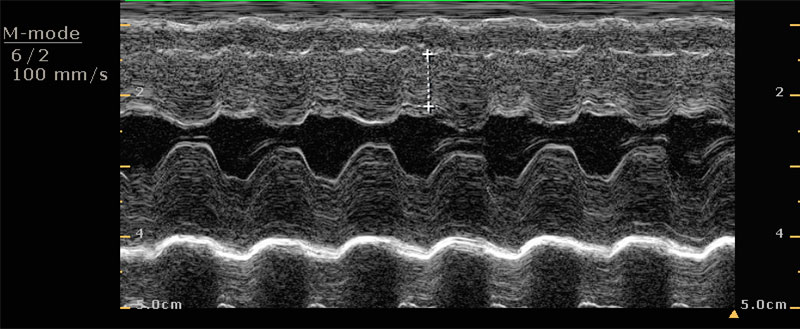

肥厚性心肌病導致血栓產生

美短右後肢突然疼痛拖行的貓咪經理學檢查懷疑為血栓造成,心臟超音波確診為肥厚性心肌病導致血栓產生,精確的診斷才有辦法良好控制疾病、保持生活品質、延長壽命。

有天主人帶著一隻美國短毛貓來診間,主人形容貓咪右後肢無法行走,後肢只能用拖行前進,經理學檢查後,我們懷疑為血栓造成,進一步用心臟超音波檢查、確診為「肥厚性心肌病」導致血栓產生,因為這樣的診斷,醫師團隊更能針對症狀給予正確的治療方式,而後貓咪也有所改善。